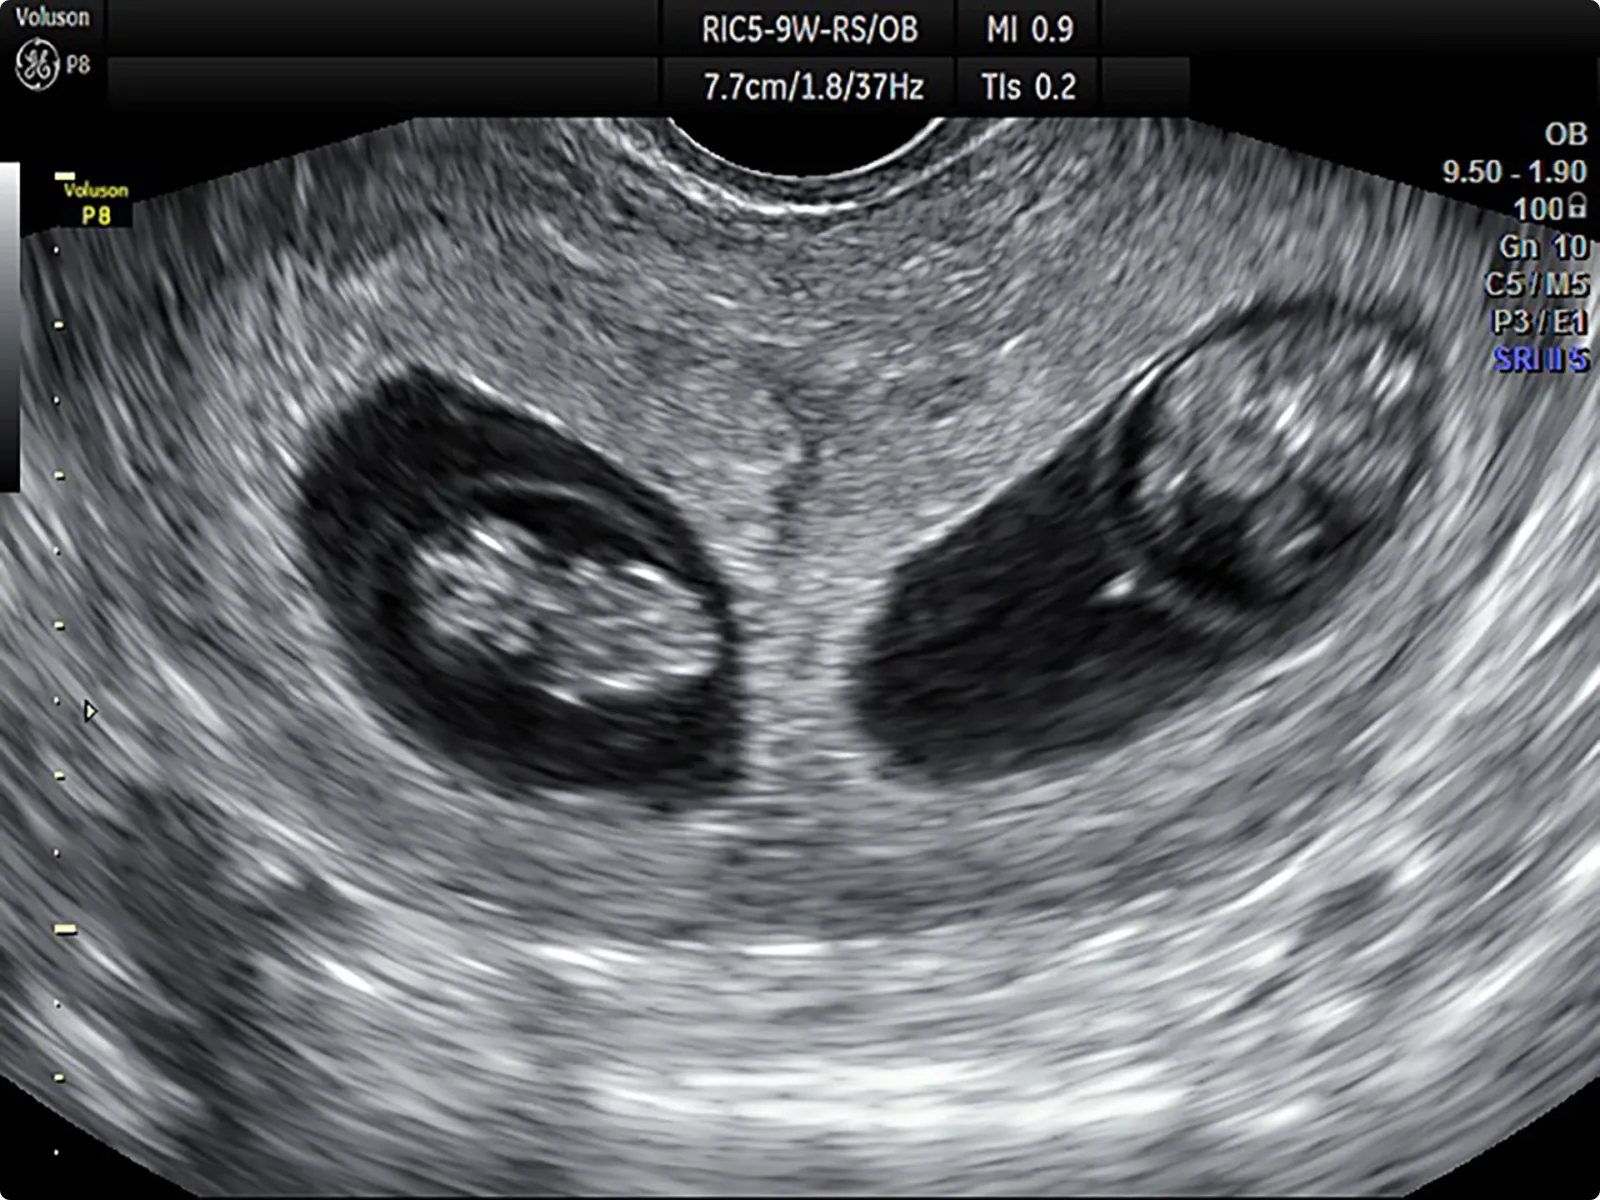

① 二絨毛膜二羊膜双胎(DD双胎)

胎児の部屋、胎盤がそれぞれに分かれています。1卵性でも起こりますが、2卵性の場合は通常このタイプなので、複数卵胞発育や複数胚移植をした場合に起こりやすいと考えられます。

DD双胎